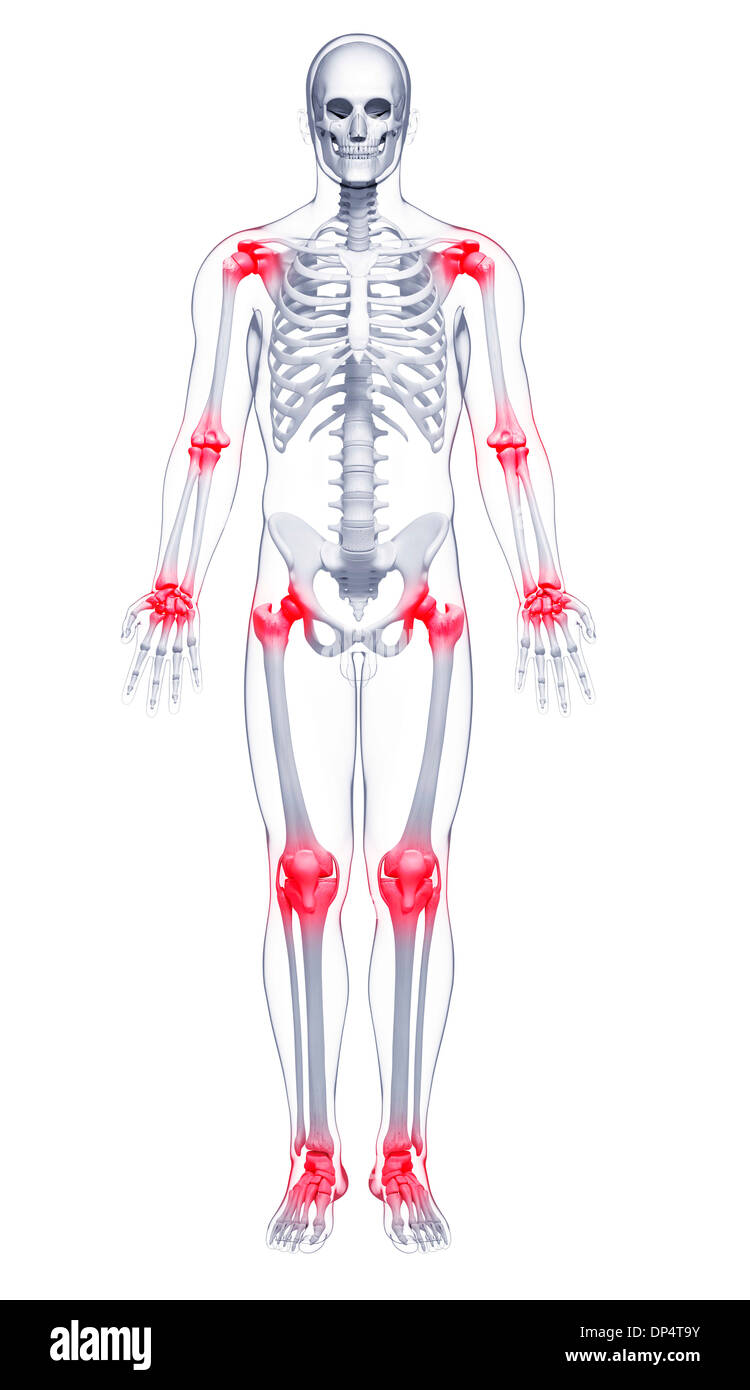

La douleur commune, artwork Banque D'Imageshttps://www.alamyimages.fr/image-license-details/?v=1https://www.alamyimages.fr/la-douleur-commune-artwork-image65260439.html

La douleur commune, artwork Banque D'Imageshttps://www.alamyimages.fr/image-license-details/?v=1https://www.alamyimages.fr/la-douleur-commune-artwork-image65260439.htmlRFDP4T9Y–La douleur commune, artwork